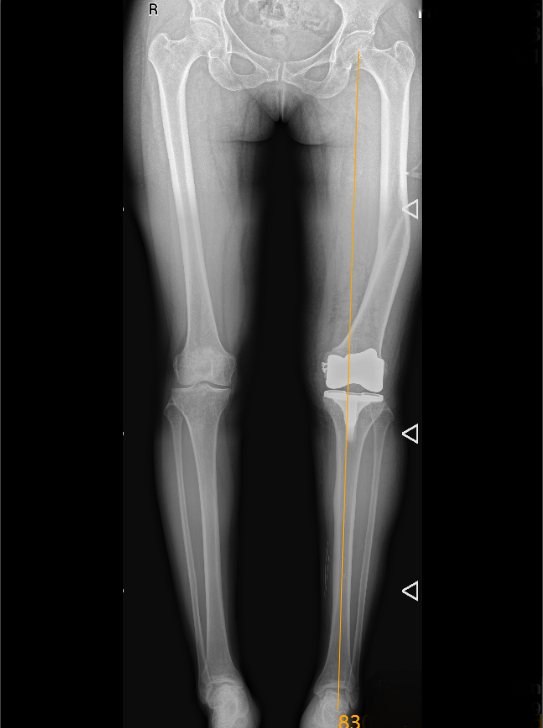

术后复查显示,王女士双下肢的力线恢复正常,膝盖伸直、弯曲都能动态平衡,假体固定得稳稳的。

更让她开心的是,多年的剧烈疼痛明显缓解,术后第二天就能下地走路了。